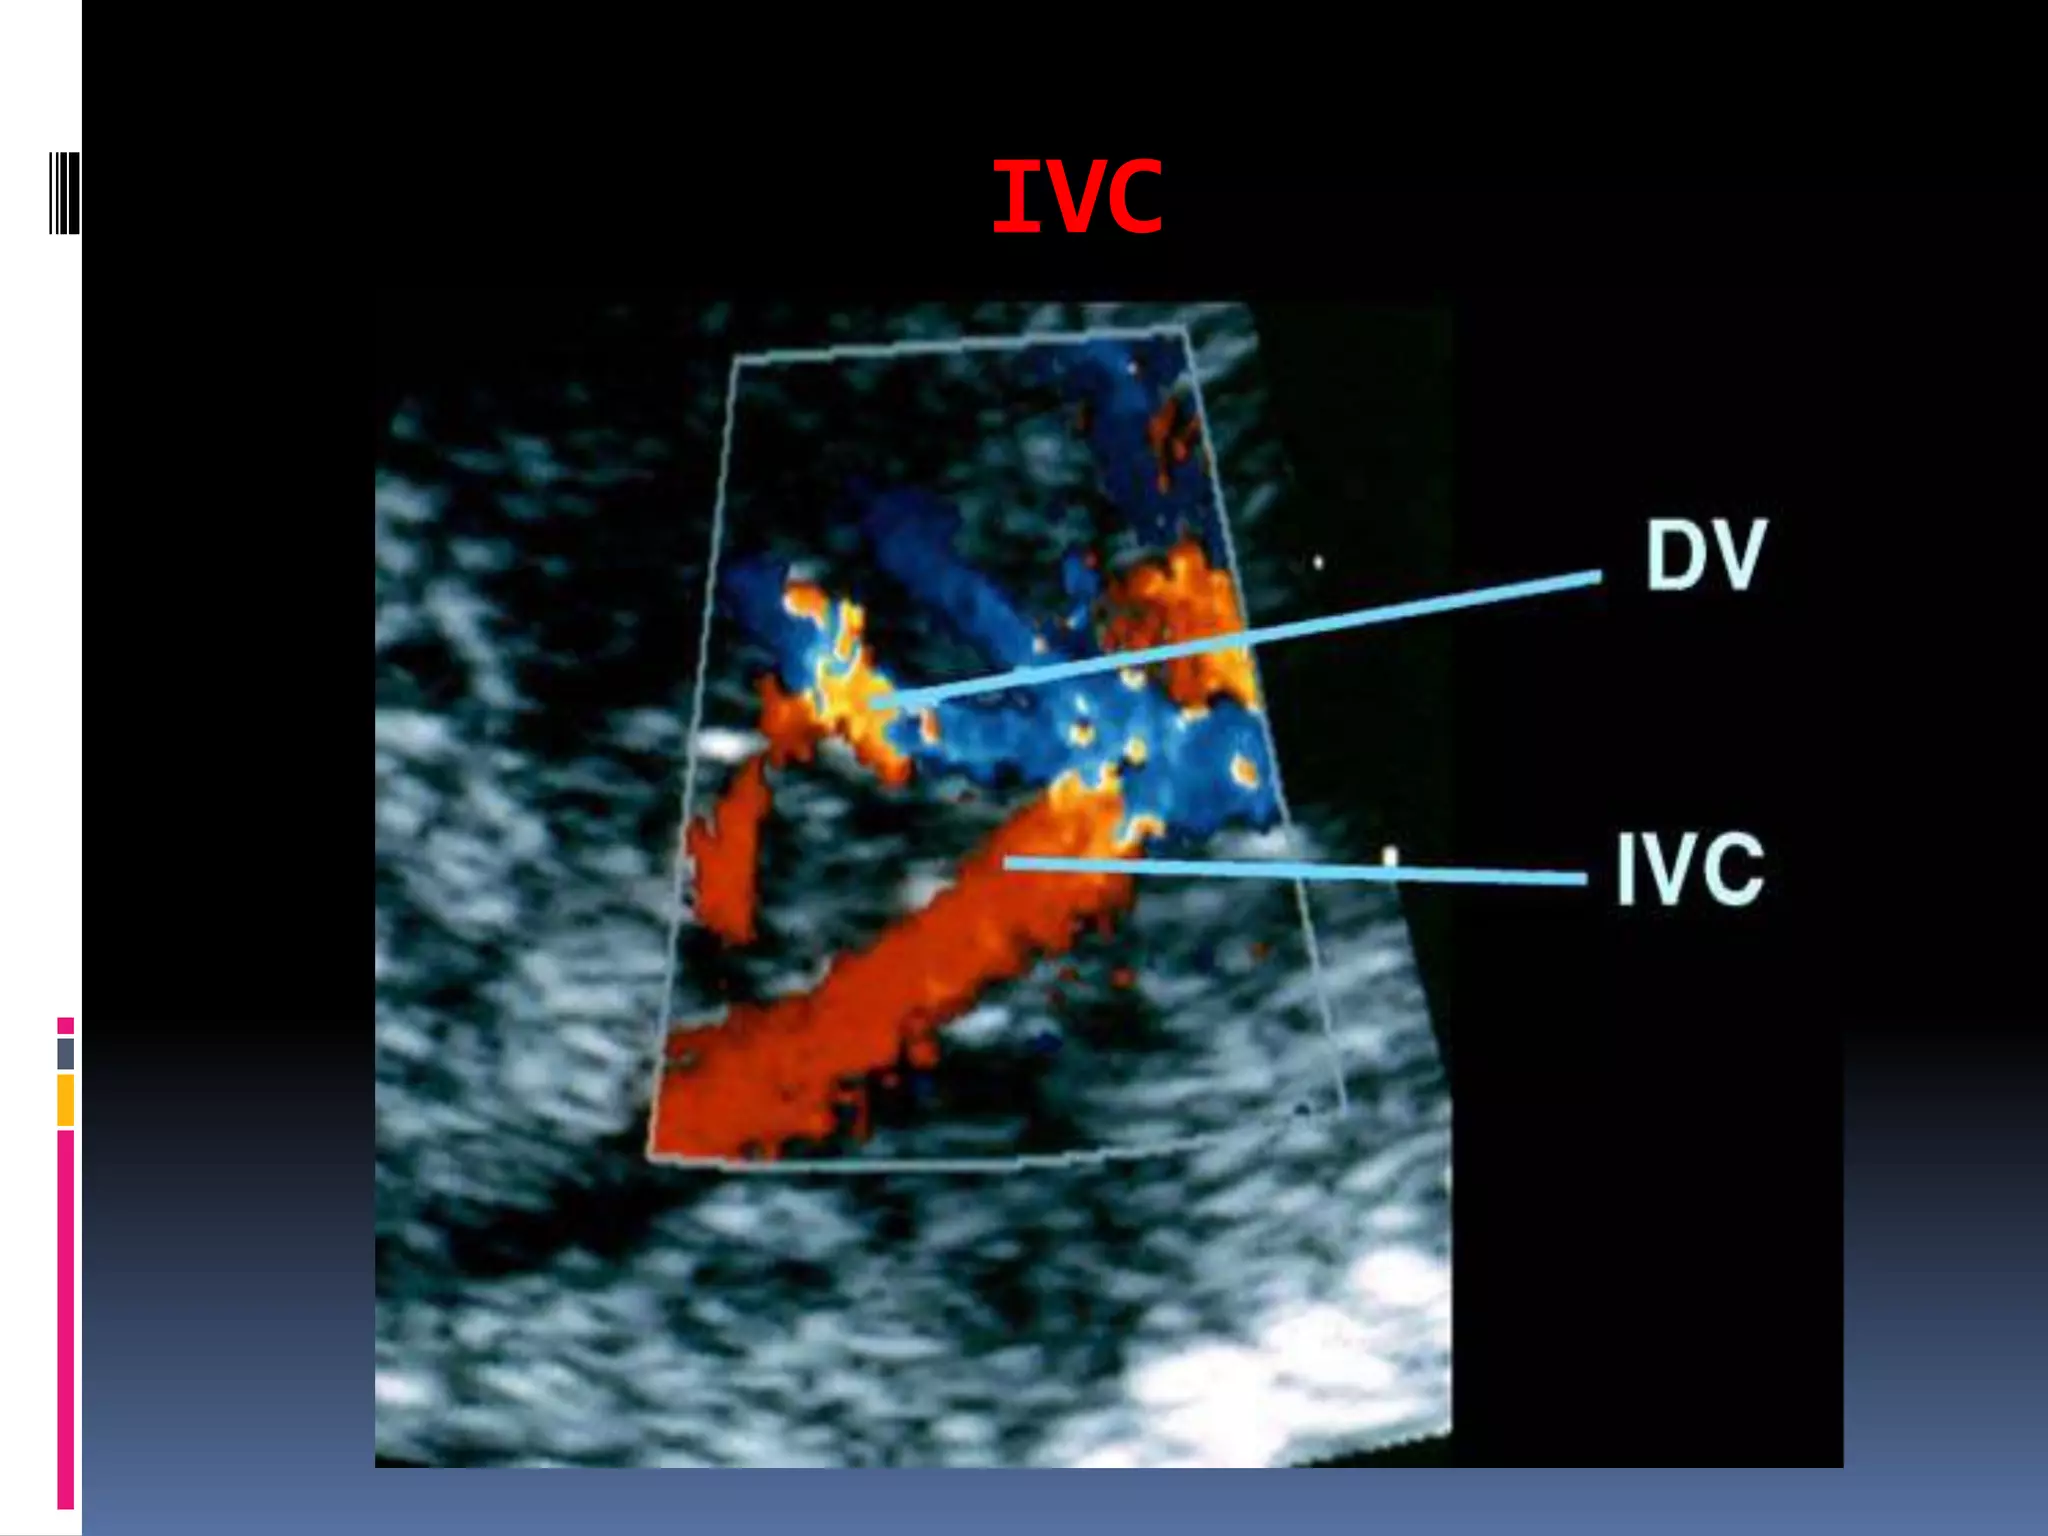

Inferior vena cava Doppler waveforms can be obtained from

a coronal plane of the chest and abdomen.

In this view, the inferior vena cava can be imaged as it

enters into the right atrium, joined by the ductus venosus

and the left hepatic vein .

The inferior vena cava can be studied at two locations: at

the inlet into the right atrium, or in the segment between

the entrance of the renal vein and the ductus venosus.

A good correlation coefficient exists between these two

measurement sites, and the location that provides the

smallest angle of insonation with the blood flow should

be chosen .

Inferior vena cava Doppler waveforms are

triphasic in shape, with the first phase

corresponding to ventricular systole, the second

phase to early diastole, and the third phase to

late diastole or the atrial kick.

IVC

Doppler velocity waveforms of the

inferior vena cava in a normal fetus in

the third trimester of pregnancy.